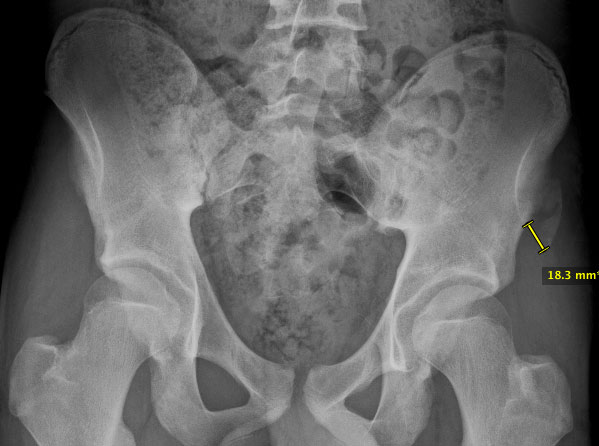

From the Journal of Paediatric Orthopaedics is a review of 228 apophyseal avulsions of the pelvis. 49% were from the anterior inferior iliac crest (AIIS), 30% ASIS, 11% ischial tuberosity, 10% iliac crest. The majority (97%) were treated non operatively.

The most troublesome group was the AIIS with ongoing pain. Failing to heal was most seen with fragments more than 20mm displaced and/or of the ischium.

They concluded that most cases are treated without surgery, and the reasons to operate are displaced AIIS fragments or gross displacement.